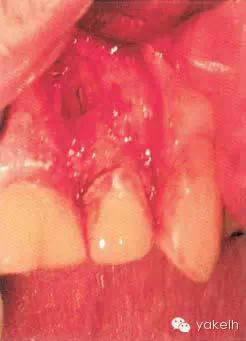

¤¤口外檢查可見(jiàn)顳下頜關(guān)節(jié)處輕微捻發(fā)音,開(kāi)口度、開(kāi)口型正常,無(wú)疼痛,未見(jiàn)其他異常??趦?nèi)檢查可見(jiàn)牙列中有部分良好的修復(fù)體,無(wú)齲壞;局部牙齦炎,探診出血,牙周探診深度不超過(guò)2mm。22唇側(cè)牙槽黏膜可見(jiàn)竇道(圖5.4.1a),輕微叩痛,竇道區(qū)捫痛,根尖X線片顯示牙根中部透射影,疑為樁穿孔(圖5.4.1b)。左上頜中切牙(21)和左上頜尖牙(23)對(duì)EPT和冷測(cè)試反應(yīng)正常。

圖 5.4.1(a)22唇側(cè)牙槽黏膜略腫。